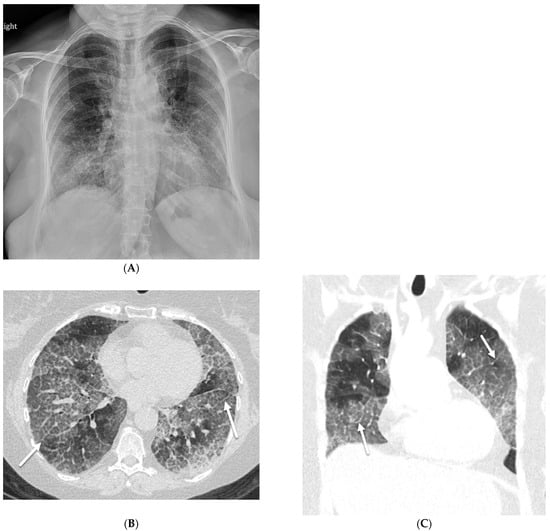

6.2. Pulmonary Alveolar Proteinosis (PAP)

| Pulmonary alveolar proteinosis (PAP) | smooth | + | ++ | + | − | − | − | +/− | − | − |

| Pulmonary alveolar proteinosis (PAP) | Tobacco use; subacute symptom onset; history of prior episodes | May occur in association with malignancies, whether pulmonary or extrapulmonary, most commonly hematologic |